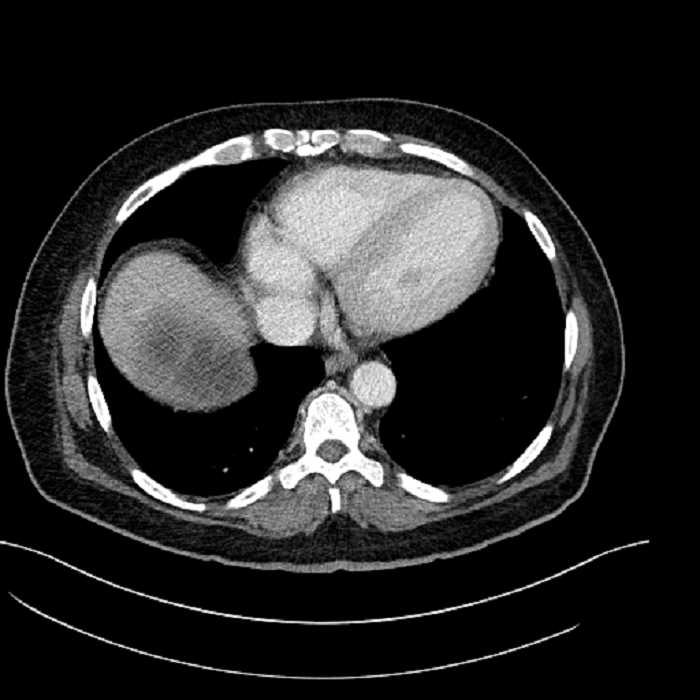

• Large fluid density structure in hepatic segments 7 and 8 measuring 10 x 7 x 7 cm with internal septation and circumferential ill-defined low density compatible with edema

• Peripherally enhancing subcapsular collections along the anterior margin of the left hepatic lobe measuring 3 x 1 cm and 2 x 1 cm

• Clearly marginated fluid density structure in segment 7 and several other scattered tiny hypodensities, which likely represent cysts

Acute sigmoid diverticulitis complicated by a small contained perforation and a large abscess in the right hepatic lobe. Additional small subcapsular abscesses along the anterior margin of the left hepatic lobe.

• The classic CT imaging appearance is a double target sign with internal low density surrounded by an internal enhancing rim (capsule) and a low density external rim (edema)

Hepatic abscess showing the double target sign with low density internally surrounded by a thin inner enhancing rim (red arrow) and ill-defined outer low density rim (yellow arrow). Blue arrow indicates an internal septation. Red arrows: additional smaller subcapsular abscesses. Red arrow: focal contained perforation associated with diverticulitis.